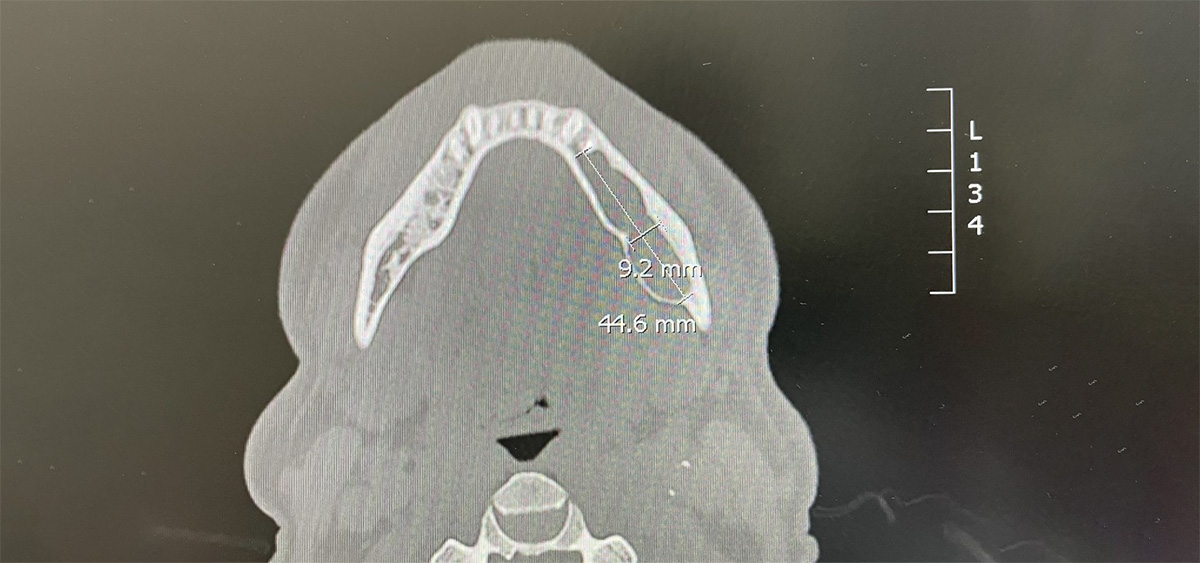

Caso di Cheratocisti in anestesia generale

Caso di Chirurgia Orale